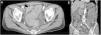

A 64-year-old man with diabetes mellitus and a 5-year history of HD was admitted to our hospital for body-fluid status evaluation because of a recent episode of intradialytic hypotension at his dialysis facility. The intradialytic hypotension was suspected to be associated with ultrafiltration-induced hypovolemia during HD before admission. NM was used several times instead of heparin sodium for retinal bleeding complicated by diabetes mellitus in his dialysis facility. At our dialysis center, HD was performed in the same manner using NM. We carefully monitored for the occurrence of ultrafiltration-induced intradialytic hypotension. His blood pressure (BP) was 195/90mmHg before HD but rapidly decreased to 114/56mmHg. The arterial oxygen saturation measured by pulse oximetry (SpO2) was 88% with dyspnea and deterioration of consciousness shortly after the HD initiation. Based on the clinical course from before admission to this episode, intradialytic hypotension with NM-associated anaphylactic reaction was diagnosed. At a later date, specific immunoglobulin E (IgE) antibodies to NM were detected in his blood. The HD therapy was discontinued to avoid further worsening of his systemic circulation. Although his BP recovered and his symptoms disappeared after HD was discontinued, he suffered from mild abdominal tenderness after the anaphylactic reaction; therefore, contrast computed tomography of the abdomen and pelvis was performed, which revealed remarkable mucosal edema at a circumference of the sigmoid colon (Fig. 1a) and along the entire intestine on a coronal view (Fig. 1b). During the next HD session using low-molecular-weight heparin, the intradialytic hypotension completely disappeared; thereafter, HD was safely performed. However, because the intestinal edema persisted on lower gastrointestinal endoscopy 2 weeks after the reaction, total parenteral nutrition instead of solid and liquid foods was necessary for approximately 3 weeks. Thereafter, he ate normally without worsening of the intestinal edema and fully recovered after 1 month of treatment.